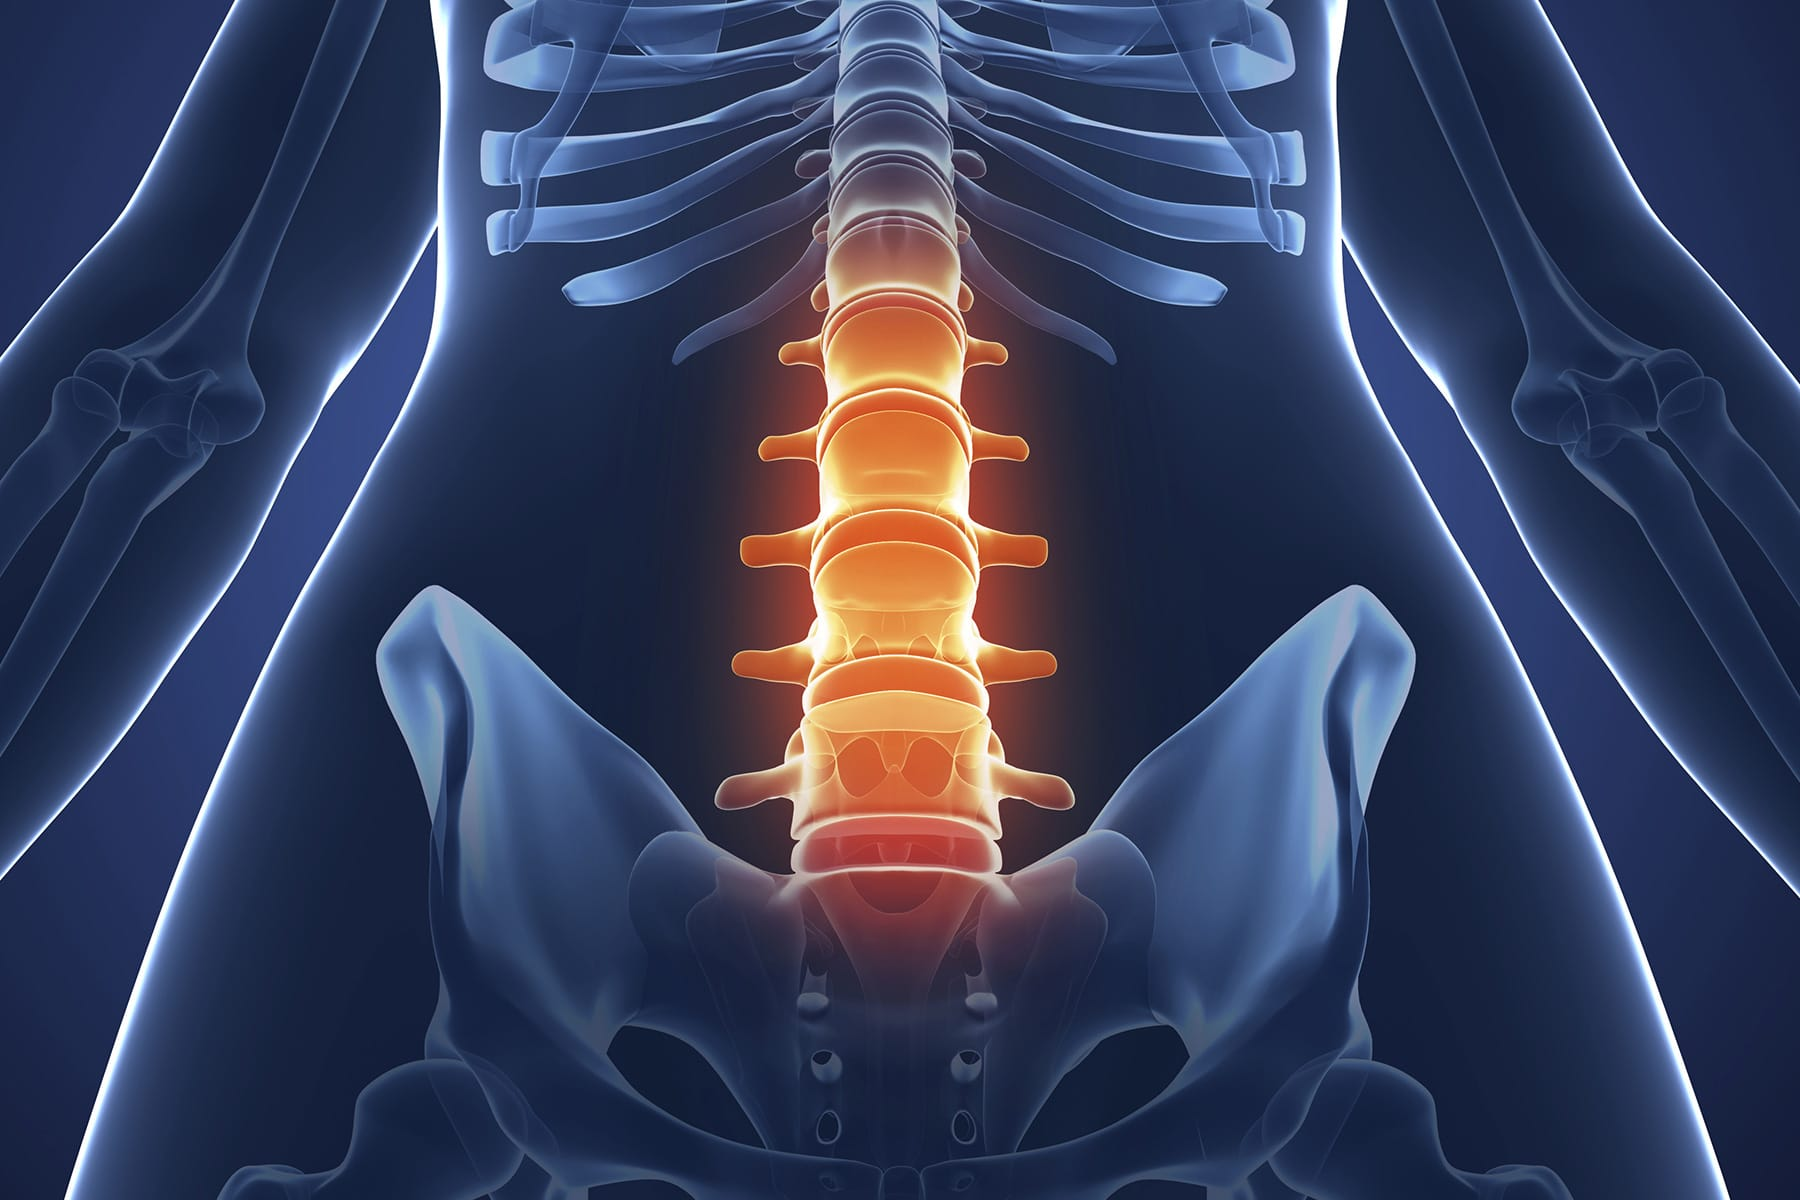

强直性脊柱炎 (AS) 是风湿科一种较为常见的关节炎,会导致脊柱疼痛和僵硬,晚期可造成脊柱强直畸形。

这种终生疾病,通常始于下背部夜间疼痛,翻身困难、严重时可影响睡眠。